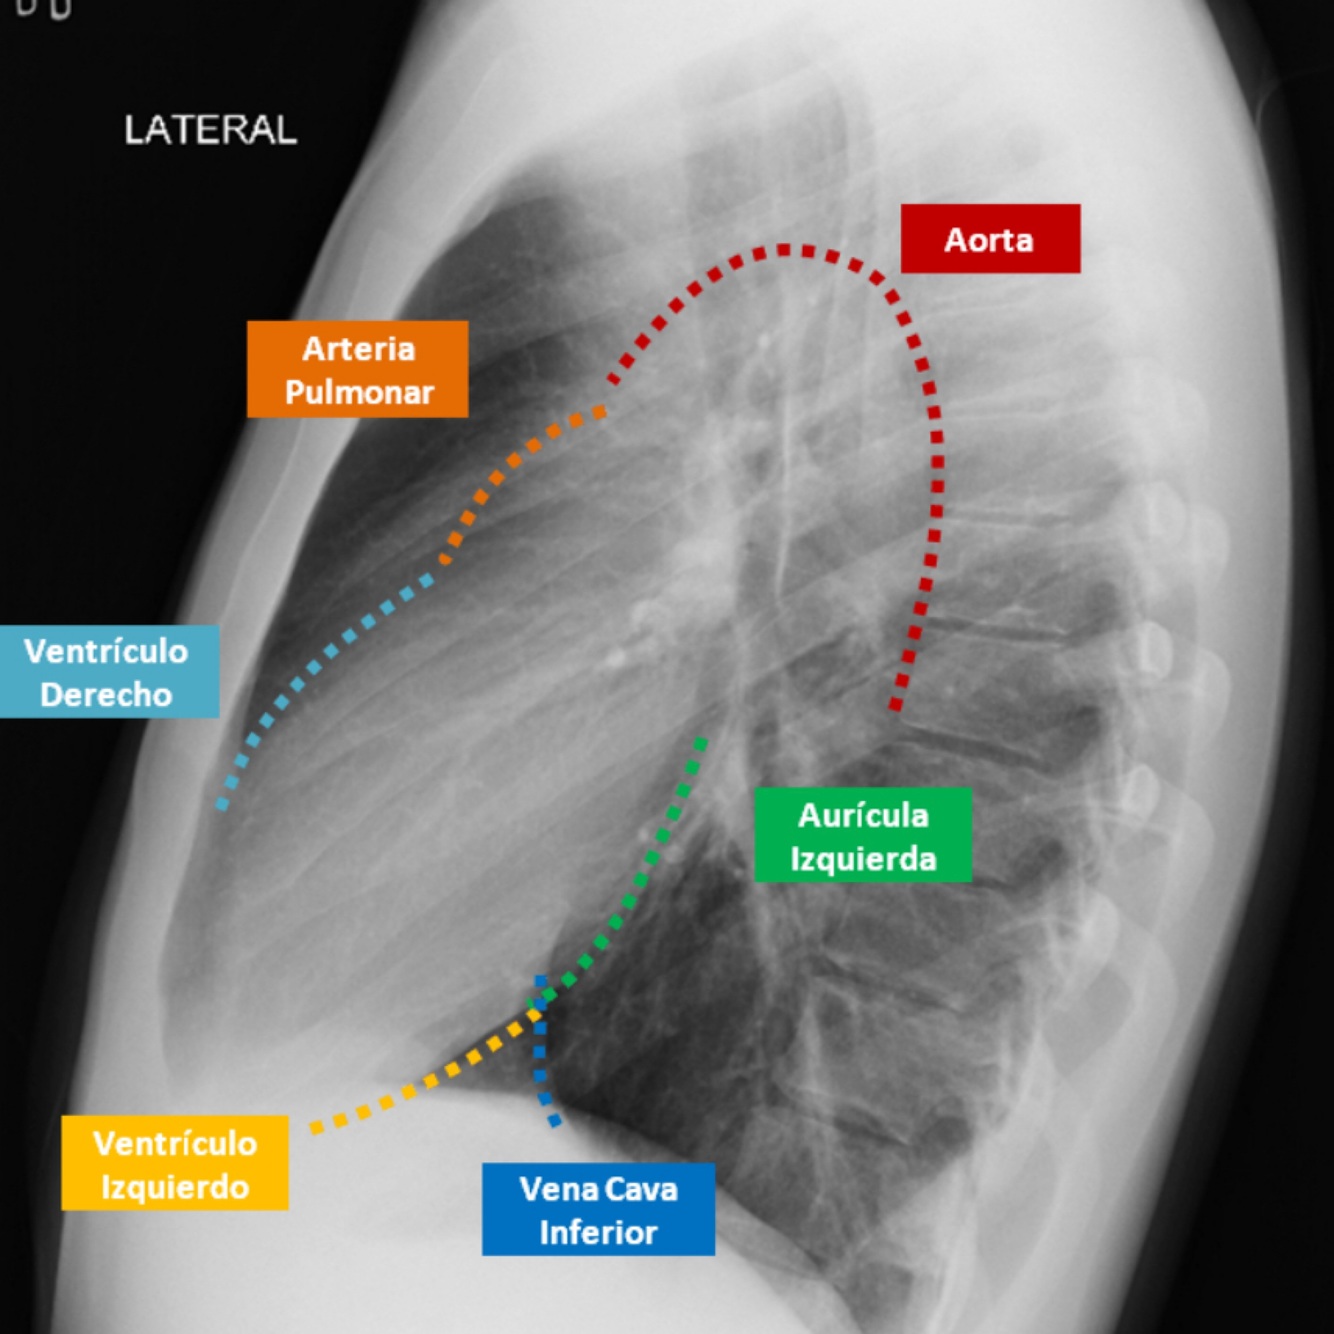

Proyecciones radiológicas

A

Postero anterior

Anteroposterior

Lateral

Oblicua

Lordotica

Q

Describe el perfil cardiaco